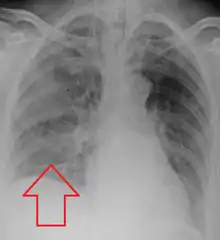

Aspiration pneumonia is typically diagnosed by a combination of clinical circumstances (people with risk factors for aspiration) and radiologic findings (an infiltrate in the proper location).[1] A chest x-ray is typically performed in cases where any pneumonia is suspected, including aspiration pneumonia.[18] Findings on chest x-ray supportive of aspiration pneumonia include localized consolidation depending on the patient's position when the aspiration occurred.[18] For example, people that are supine when they aspirate often develop consolidation in the right lower lobe of the lung.[18] Sputum cultures are not used for diagnosing aspiration pneumonia because of the high risk of contamination.[19] Clinical symptoms may also increase suspicion of aspiration pneumonia, including new difficulty breathing and fever after an aspiration event.[6] Likewise, physical exam findings such as altered breath sounds heard in the affected lung fields may also be suggestive of aspiration pneumonia.[6] Some cases of aspiration pneumonia are caused by aspiration of food particles or other particulate substances like pill fragments; these can be diagnosed by pathologists on lung biopsy specimens.[20]